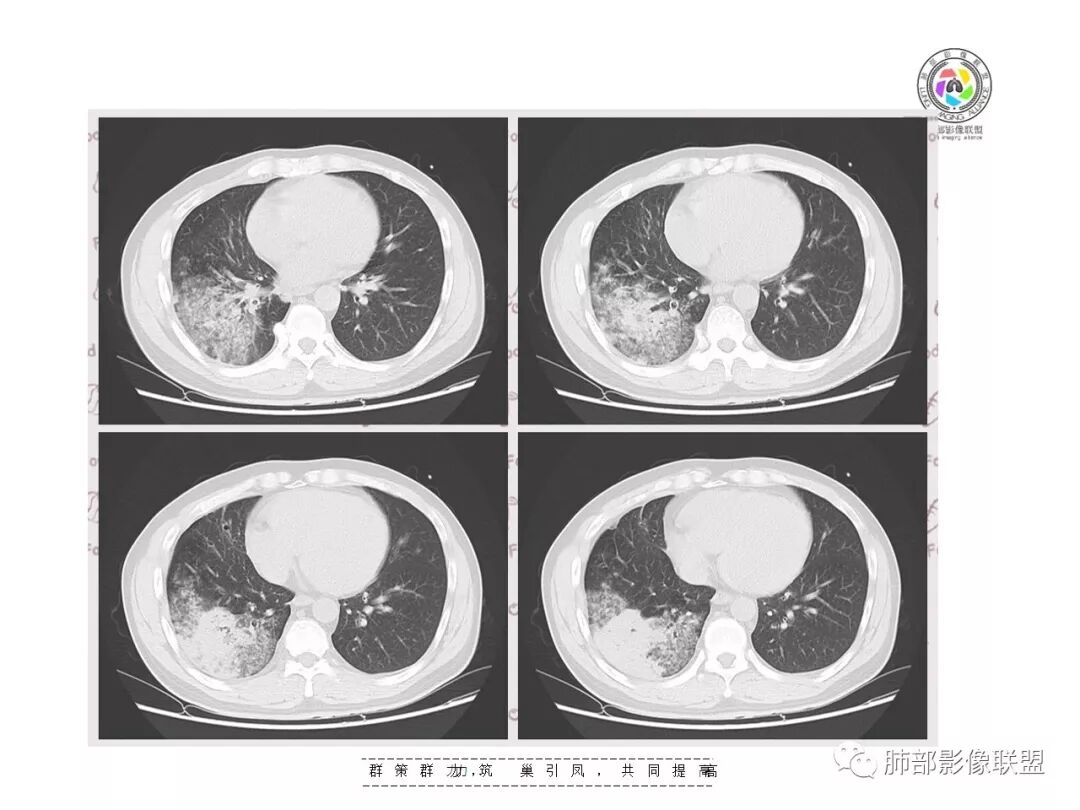

【影像资料】

GGO边界大部分不清楚,内有树芽征,中央间质均匀增厚

如果单独讨论这个病灶:我倾向于急性感染性病变

因为病灶的分布就是沿支气管走形,病灶整体就是沿段分布

实变区边界清、凹陷及平直,内部密度均匀,强化均匀,支气管在密实处填塞,其余部分通畅、走形自然,中央间质均匀增厚

GGO均匀,边界模糊,树芽征

但是问题来了:淋巴结

南边:

右肺门区淋巴结增大,融合,密度均匀,均匀强化

符合这个特点的:结核?淋巴瘤?转移瘤?

淋巴结我觉得目前的特点:淋巴瘤?结核?